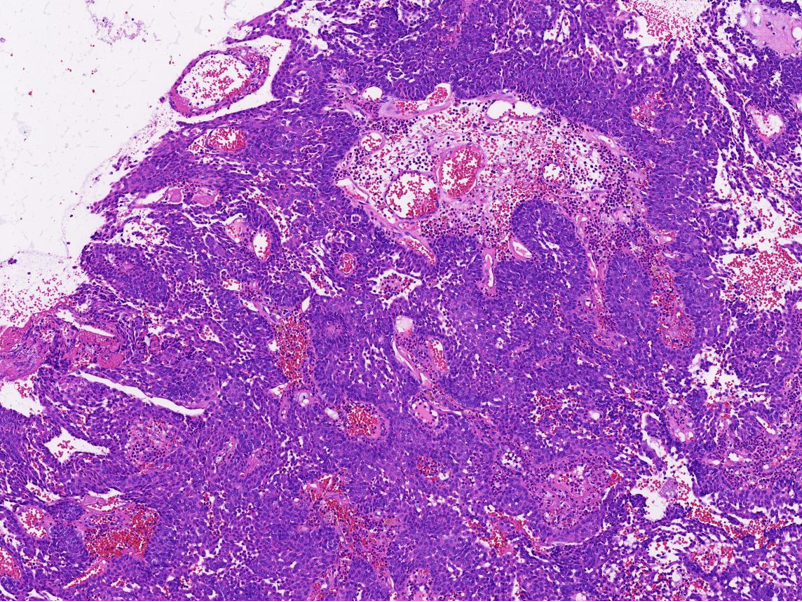

下半场,进行了《淋巴瘤良恶性鉴别诊断基础》的学术讲座。